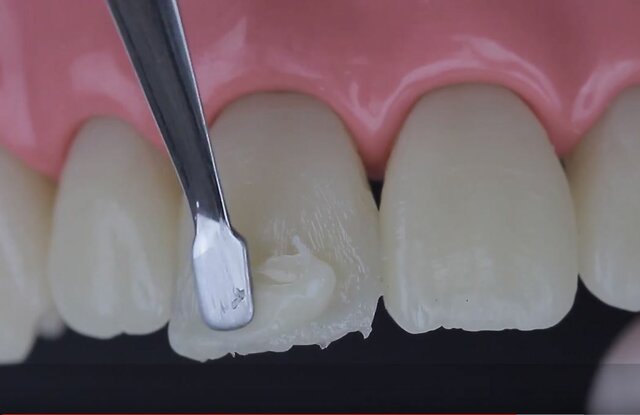

• Primera resina compuesta

Primera resina compuesta

Ray Bowen sintetiza la primera resina compuesta, o composite, para utilizarla como material de obturación de los dientes. El composite permite otorgar distintas tonalidades hasta acercarse al color natural del diente del paciente.